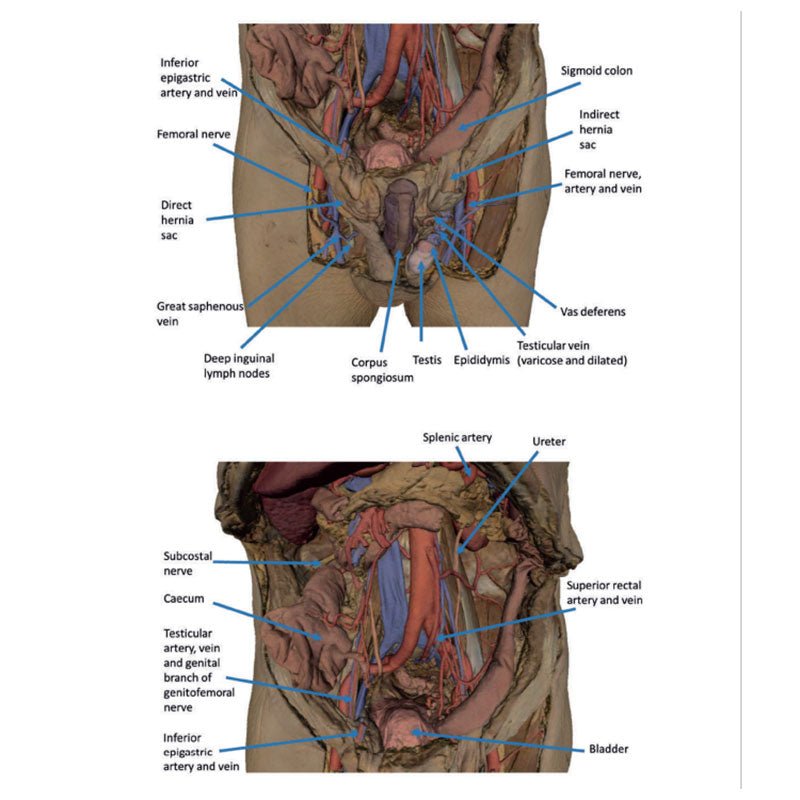

The hypogastrium and iliac regions

In the midline, the bifurcation of the descending abdominal aorta into the

common iliacs (and subsequent division into the internal and external iliacs) can be observed deep to some of

the overlying structures (e.g., testicular vessels, ureters) noted previously. On the right side, the obturator

artery can be seen traversing from its origin towards the anterior aspect of the pelvis. The mirrored merging of

external, internal and common iliac veins into the inferior vena cava is also preserved. Within the confines of

the true pelvis the peritoneum has been retained over the region, covering the urinary bladder adjacent to the

pubic symphysis and obscuring the rectum as it descends from the sigmoid colon. In the right iliac region the

very terminal part of the ileum and caecum with appendix fill the iliac fossa, with the appendix (and

appendicular artery) visible just superficial to the testicular artery, vein and genital branch of the

genitofemoral nerve descending towards the inguinal canal. In the left region, the sigmoid colon descends across

the iliac fossa. As it approaches the anterior abdominal wall, an epiploic appendage contribution to the

indirect hernia can be observed just lateral to the retained inferior epigastric artery.

The inguinal region and perineum

A distinctive and unique feature of this model is the dissection of

simultaneous direct and indirect hernias preserved on the right and left sides, respectively. While most of the

anterior abdominal wall has bee removed, the inferior epigastric arteries (and accompanying veins) have been

retained to allow for interpretation of the herniations. On the right side, a distinct outpouching of the

parietal peritoneum has formed medial relative to the inferior epigastric artery, representing an indirect

herniation event. On the left side, the hernia sac extends laterally relative to the inferior epigastric artery

and into the opened spermatic cord, with continuity of the epiploic appendage from the sigmoid colon into the

The skin over the perineum has been removed in order to demonstrate both the structure of the penis

(with both the corpus spongiosum and corpora cavernosa contrasted) and the position of the testes and spermatic

cords relative to the anterior abdominal wall. On the right side, which in this individual is impacted by a

direct hernia, the spermatic cord has been left undissected allowing for an appreciation of the external

spermatic fascia from the inguinal region through to the testis. On the left side, the spermatic cord has been

opened and is dominated by the enlarged and varicose testicular vein (reflecting the impact of the indirect

hernia exposed within the cord) just superior to the epididymis and exposed tunica albuginea of the testis.

The thigh

Anterior dissections into the femoral triangle region have been undertaken to both thighs with

varying preservation of contents. On the right side the femoral sheath has been removed to expose the femoral

artery, vein and the deep inguinal lymph nodes. The femoral artery has been sectioned with a portion removed to

expose the origin of the profunda femoris and to better appreciate the draining of the great saphenous vein into

the femoral vein. Just lateral to these structures the very terminal component of the femoral nerve is visible.

On the left side a slightly larger dissection window has been opened to expose more of the underlying anterior

and medial thigh compartment muscles, from the sartorius and iliopsoas laterally to the pectineus and adductor

longus medially. The femoral artery has been preserved, with a well-preserved superficial circumflex iliac

artery and the origin of the profunda femoris visible adjacent to the femoral nerve.